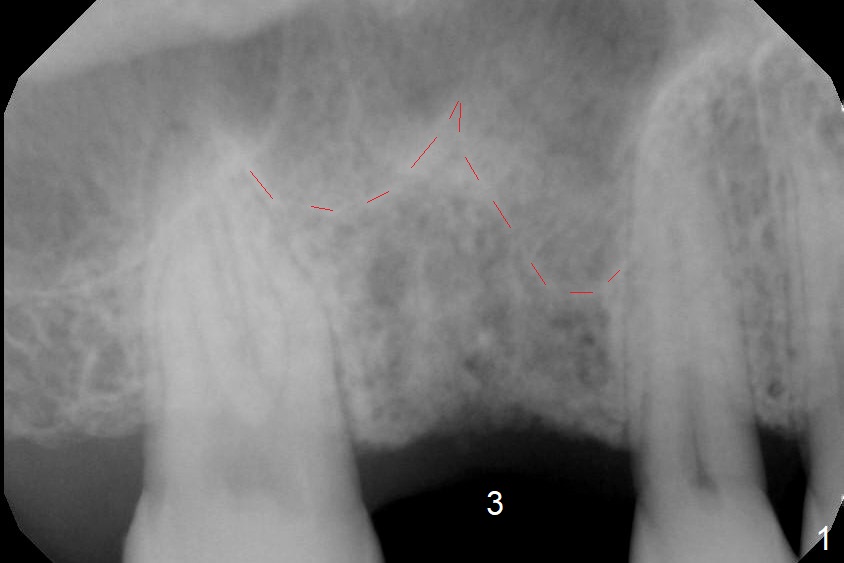

A 54-year-old man has lost the tooth #3 for 6 months with complicated sinus floor morphology (Fig.1 red dashed line (one of 2 outlines), bone height ~ 7 mm). Initial osteotomy depth is ~ 6 mm (Fig.2,3 with 1.2 mm initial drill and DIO Bone Expander 1 (E1 with diameter 1.0/1.6 mm). Following change in the trajectory, E2 (1.3/2.3 mm) is used for ~ 8 mm (Fig.4). After application of E4 (2.4/3.7 mm, Fig.5) and E5 (3.0/4.4 mm) for ~ 12 mm, the sinus membrane is found to have perforated. With placement of collagen membrane and cortical allograft (Fig.6 *), a 5x8.5 mm Hiossen implant is placed with >50 Ncm.